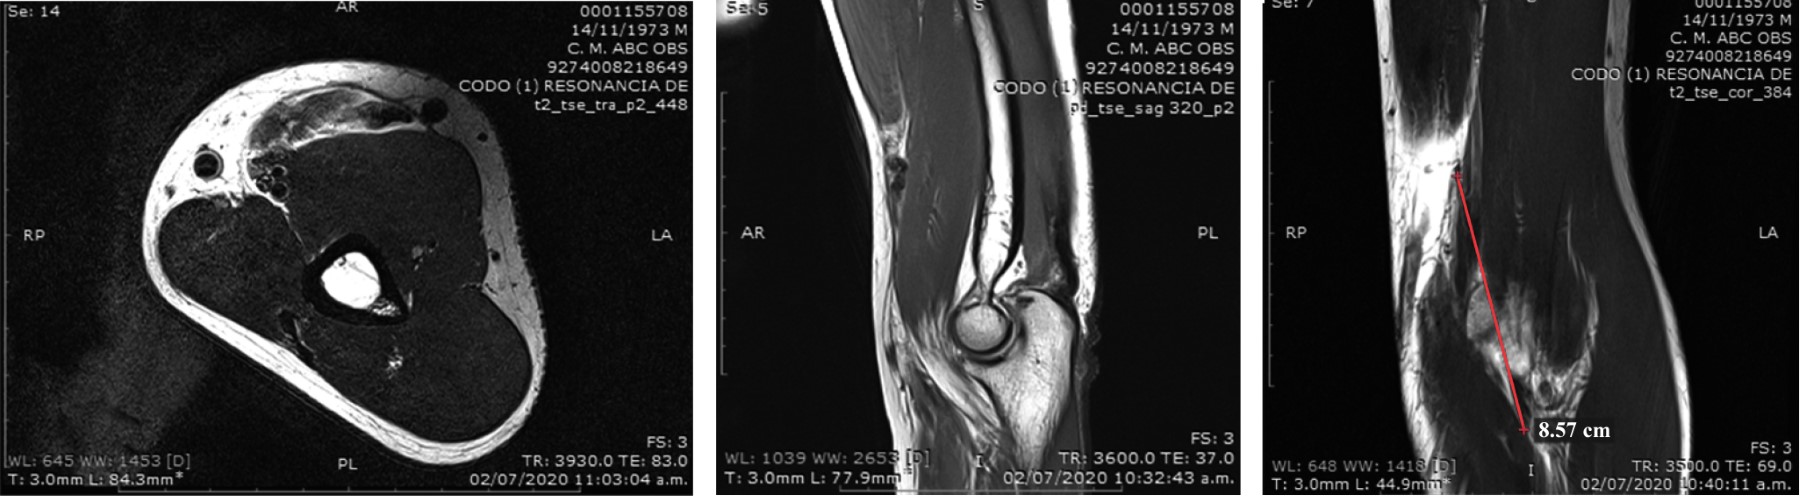

Distal biceps brachii rupture in a patient with COVID-19

Cuéllar-Avaroma A, King-Martínez M, Martínez-Oliva D, Rodríguez-Zulueta P, King-Martínez A

Introduction: distal biceps tendon injury commonly occurs in male patients between the fifth and sixth decade of life. The mechanism of the injury is an eccentric contraction with the elbow in flexion of 90 degrees. For its surgical treatment, several options have been described in the literature with different approaches, type of suture to be used and various methods of fixing the repair of the distal biceps tendon. The musculoskeletal clinical manifestations of COVID-19 are fatigue, myalgia, arthralgia, but the musculoskeletal effects of COVID-19 remain unclear. Case report: 46-year-old COVID-19 positive male patient with acute distal biceps tendon injury and secondary to minimal trauma, with no other risk factors. The patient was treated surgically following orthopedic and safety guidelines for the patient and medical staff due to the COVID-19 pandemic. The surgical procedure of the double tension slide (DTS) technique with a single incision in a reliable option and our case of a low morbidity, few complications and a good cosmetic option. Conclusion: the management of orthopedic pathologies in COVID-19 positive patients is increasing as well as the ethical and orthopedic implications of the management of these injuries and/or the delay of their care during the pandemic.

Figure 1